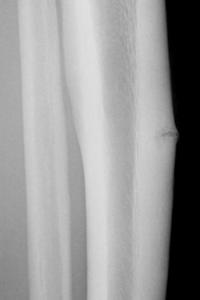

疲労骨折が生じる部位はスポーツの種目によって大体決まっています。サッカー選手における足の外側の骨(第5中足骨)や、バレーボールや走り高跳びなど跳躍系の選手や長距離ランナーにおけるすねの骨(けい骨)、ゴルファーにおけるあばら骨(肋骨(ろっこつ))、剣道やテニス選手における腕の骨(尺骨)などが代表的なものです。この中ではけい骨が最も多く発生します。

症状としては骨折ですから当然痛みがあります。しかし通常の骨折と異なるのは、脚の疲労骨折の場合は歩くことができます。そのため患者さん本人や周囲の人は歩くことができるから骨折はないと判断してしまいがちです。また、初期の疲労骨折は単純X線写真では異常が出ません。そのため医療機関を受診しても練習のやり過ぎによる慢性の筋肉痛などと診断されてしまうことがあります。

単純X線写真で疲労骨折とわかるのは、症状が出てから約2週間といわれています。疲労骨折の早期発見のためには磁気共鳴画像装置(MRI)や核医学(RI)検査が有用です。